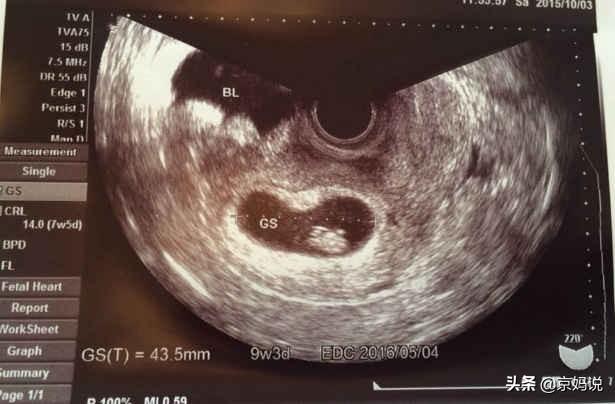

Une échographie réalisée entre la 7e et la 8e semaine de grossesse pour déterminer si le fœtus est intra-utérin et le développement du cœur et des bourgeons du fœtus peut aider la mère à se sentir un peu plus détendue.

- Généralement à partir deElle apparaît vers la 6e semaine de grossesse et continue à s'atténuer jusqu'à la 12e semaine de grossesse, et bien sûr, certaines femmes enceintes vont jusqu'à la 16e semaine de grossesse.。